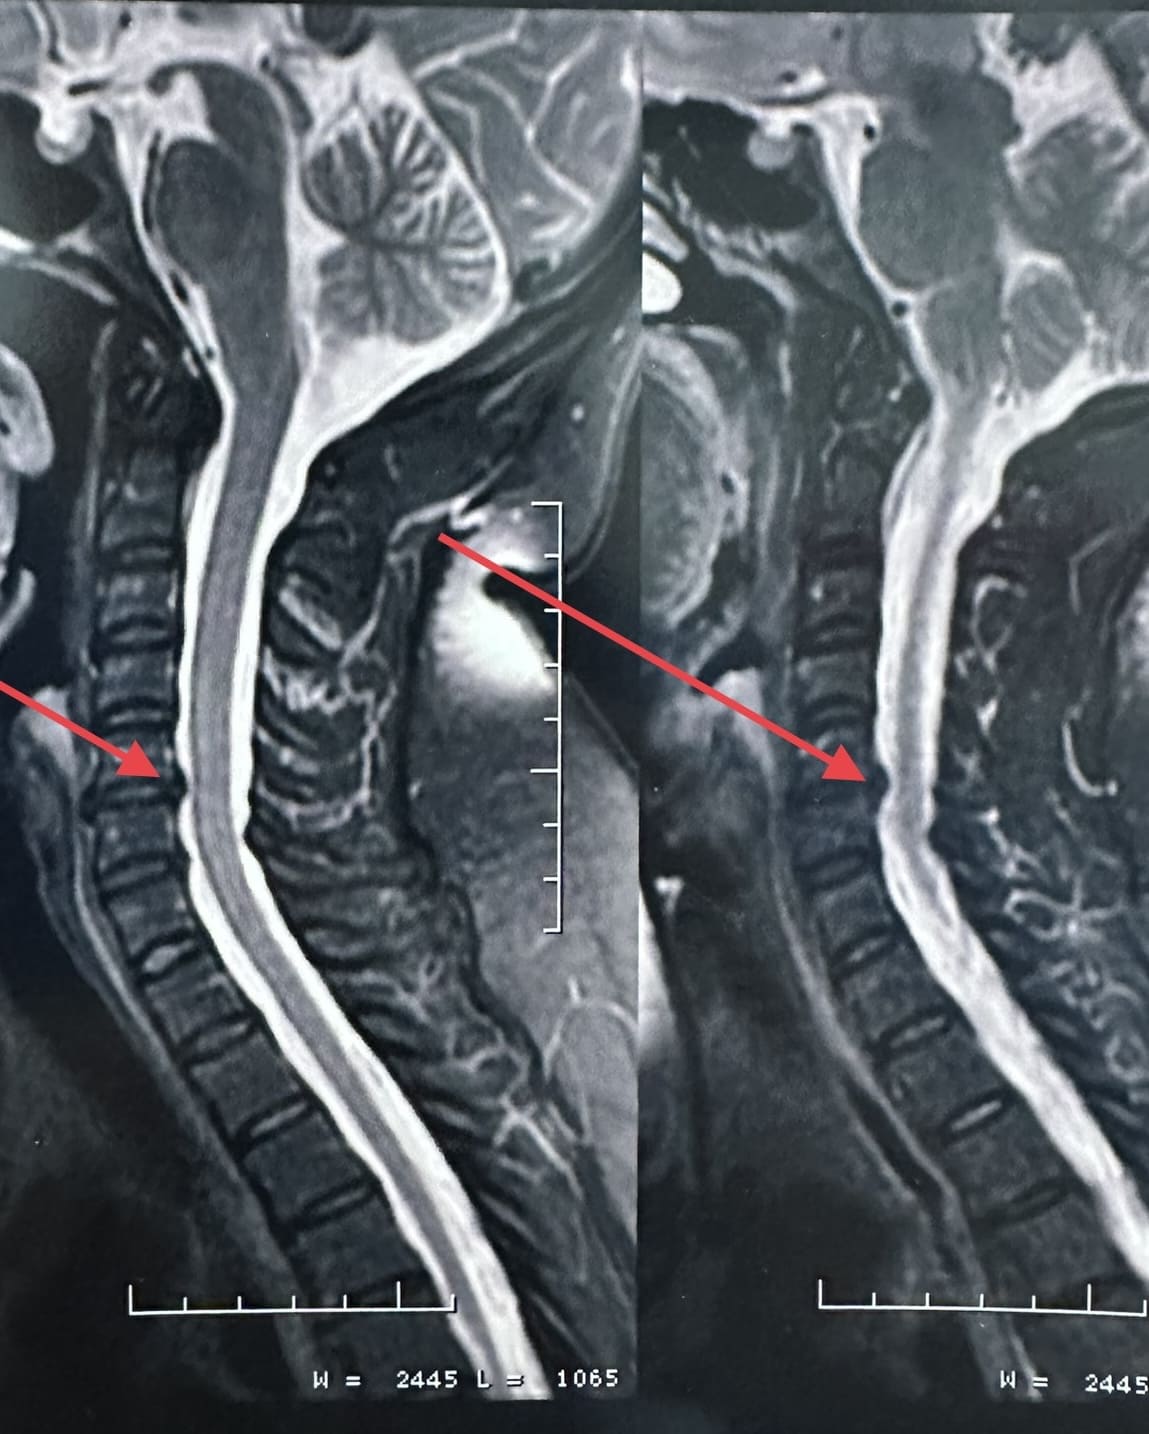

Uma hérnia de disco cervical ocorre quando o material do disco intervertebral se desloca ou se projeta para fora de sua posição normal e comprime as estruturas circundantes, como os nervos ou a medula espinhal.

Exames como ressonância magnética (RM), tomografia computadorizada (TC) e radiografias são frequentemente realizados para diagnosticar a condição da coluna cervical antes de decidir pela cirurgia.